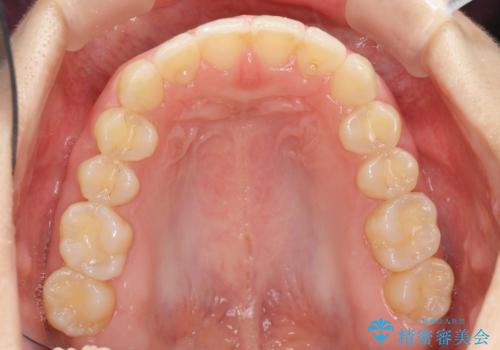

出っ歯に見える前歯の改善 部分ワイヤーとマウスピース矯正

- 出っ歯に見える前歯の改善を希望され、来院されました。

マウスピースでは改善の難しい歯の動きを部分ワイヤー矯正で整えたのち、奥歯の噛み合わせや細かい歯の並びをマウスピース矯正インビザラインで整えていきます。

最終的な前歯の並びに大変満足いただくことができました。